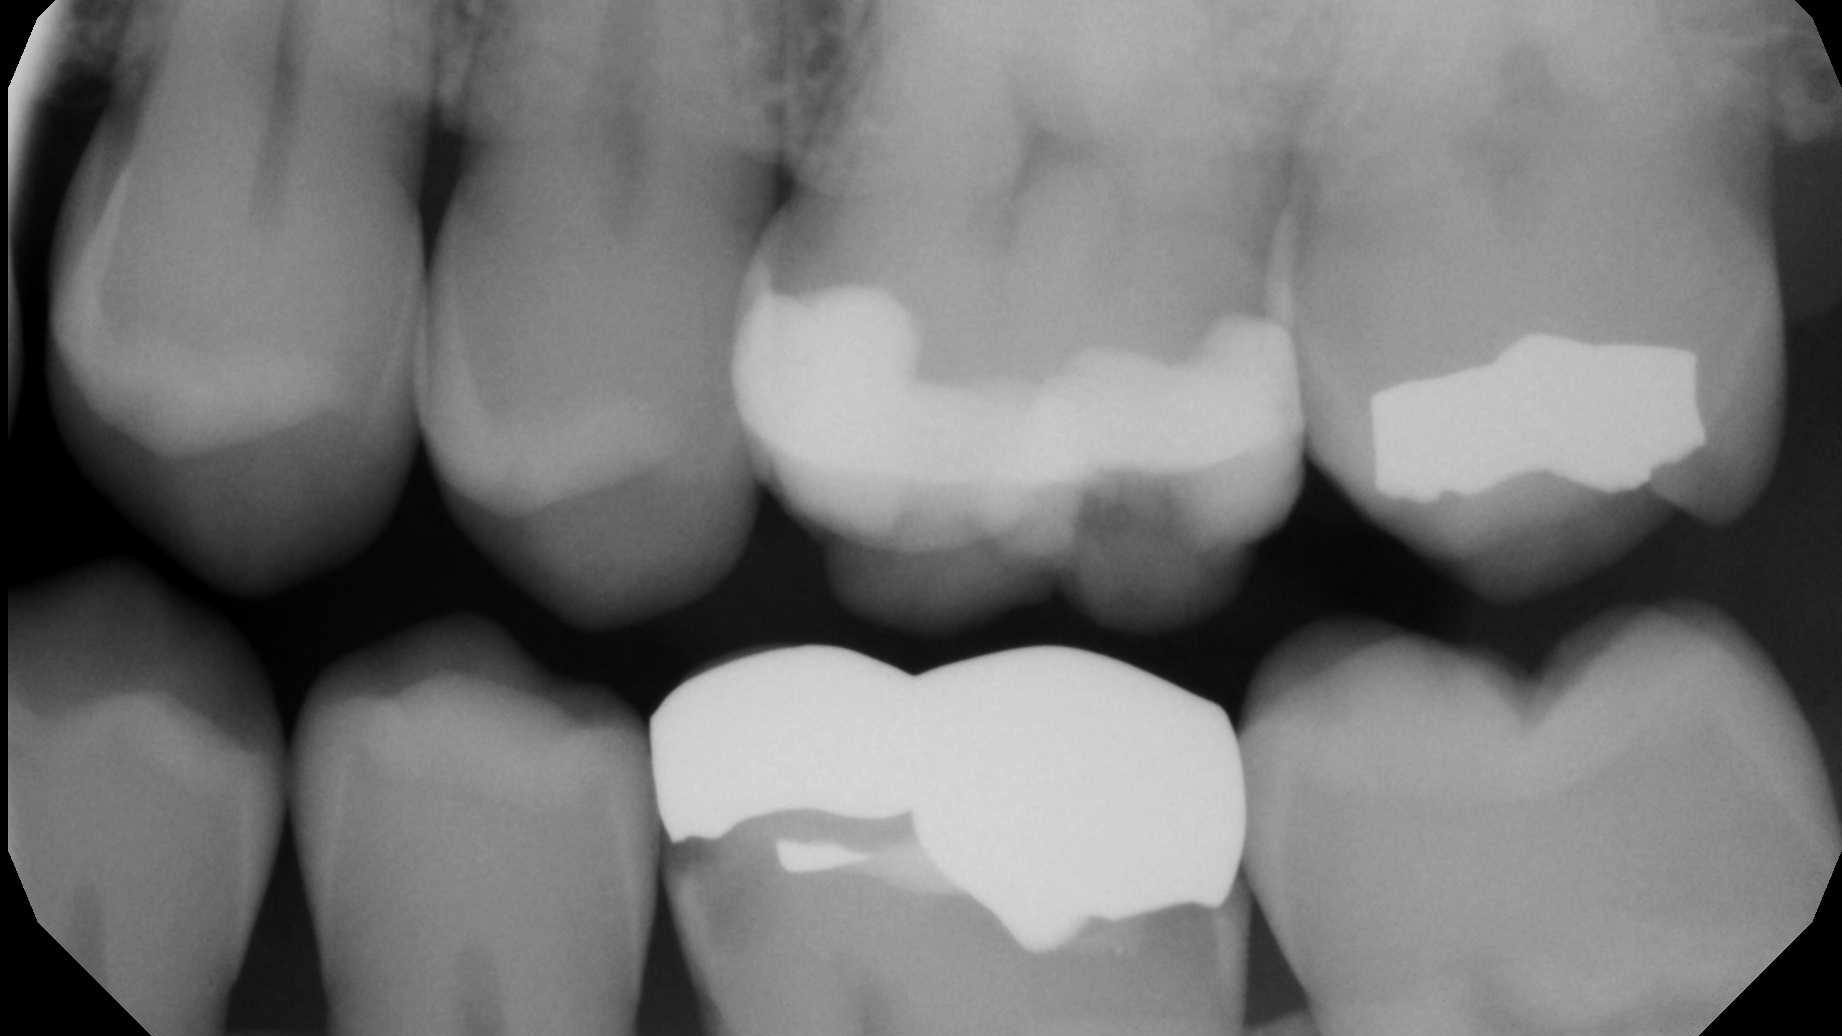

Just this week, I saw a patient for a recare exam who had decay under the mesial margin of a gold onlay I placed seven years ago. I looked back through the sporadic bitewings from the past several years, and sure enough, there it was—small at first and growing as my denial grew with it (figures 1 and 2).